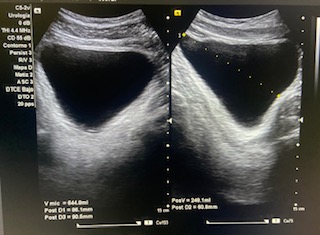

Vejiga bien repleccionada sin alteraciones a simple vista.

Volumen residual: 243 ml. Próstata de contornos regulares y ecogenicidad homogénea a simple vista. Volumen prostático: 49 cc.

En ecografía determinamos el tamaño de la próstata mayor de 20 cc, por tanto se trata de una HBP grado II. La medición del RPM nos permitió detectar que el paciente presentaba residuos elevados (243 ml).